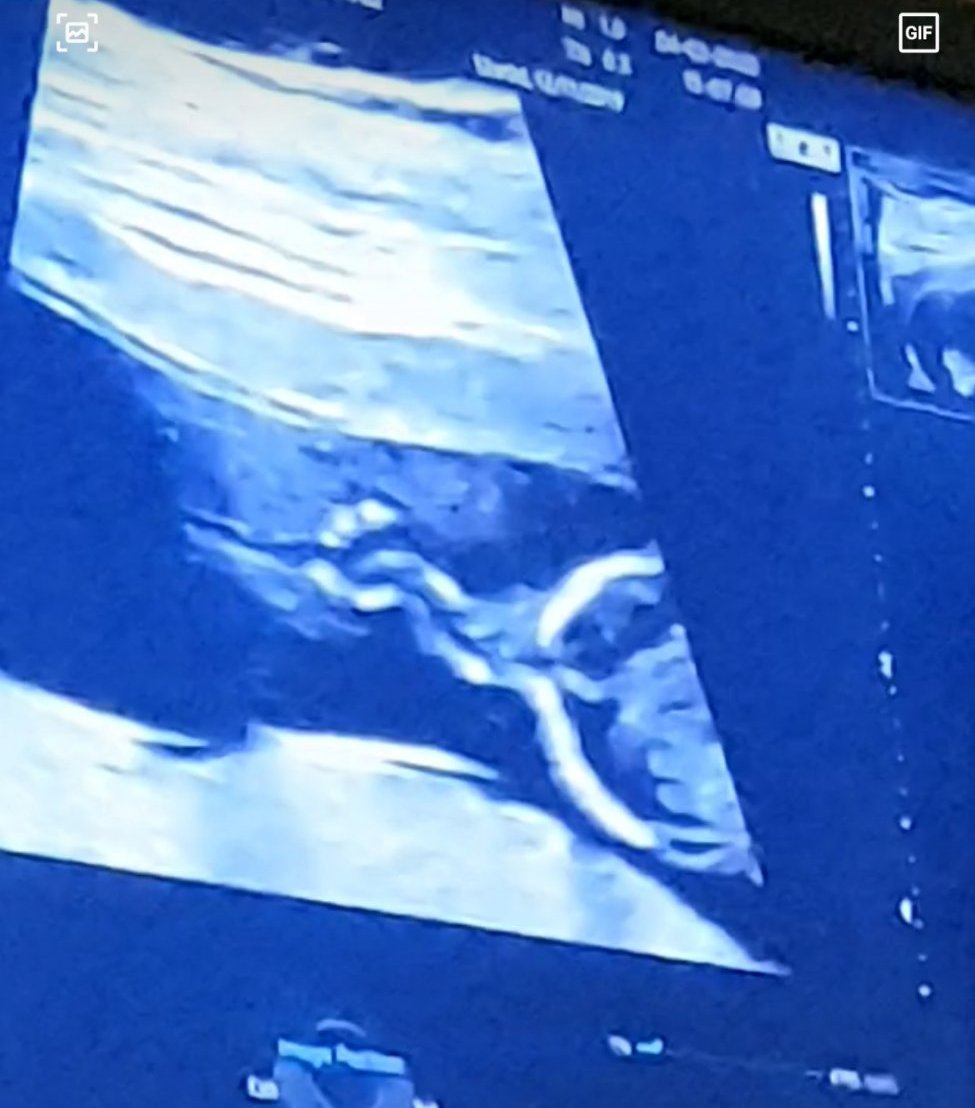

Здравейте!Бях на ФМ в 12.г.с. и докторката се усъмни за шесто пръстче на едната ръка.Възможно ли е на този етап да се вижда толкова добре?БХС е идеален

През корема,това е ръчичката